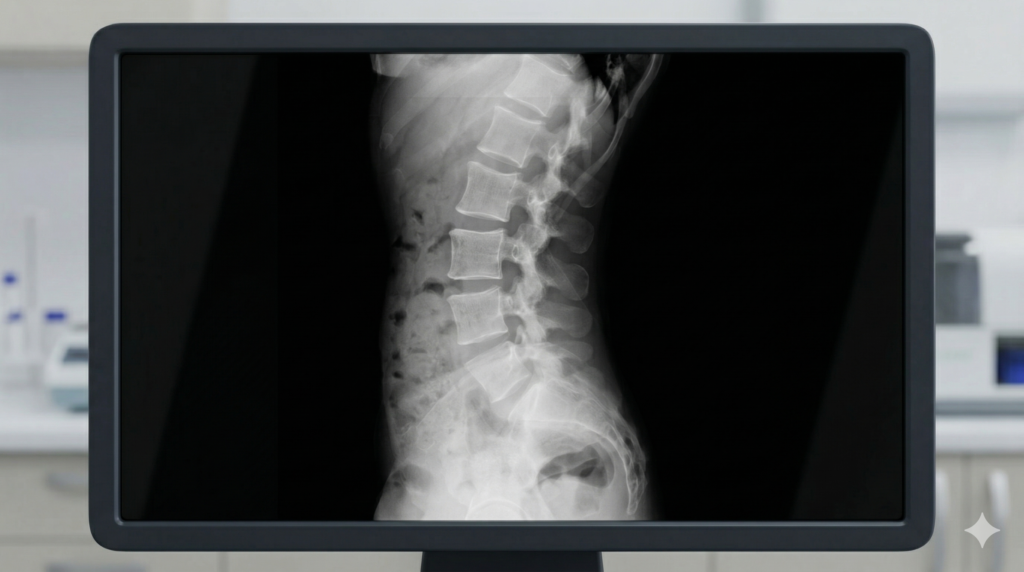

Espondiloartropatías

Diagnóstico y tratamiento de espondilitis anquilosante, artritis psoriásica y artritis reactiva. Enfoque en control del dolor, movilidad y calidad de vida.